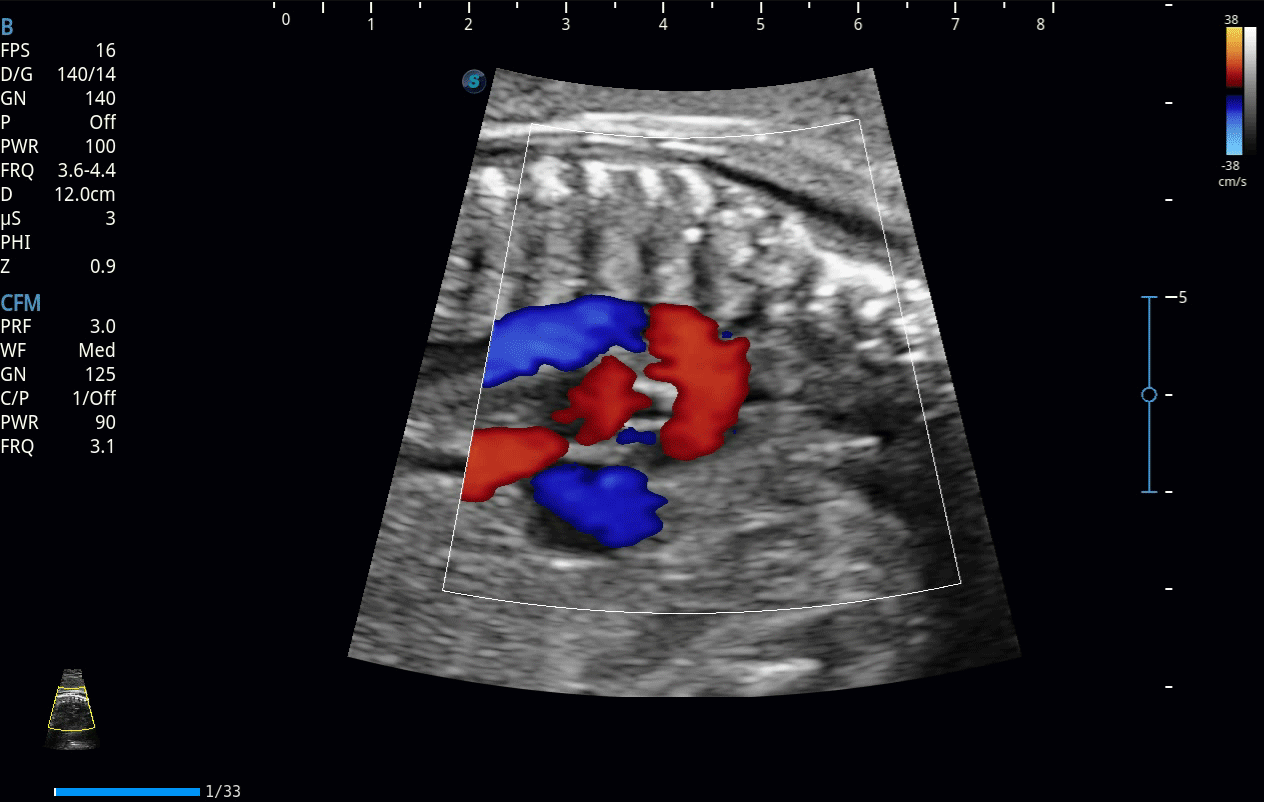

開立醫(yī)療通過不斷的技術(shù)創(chuàng)新,為大眾的生命健康提供持續(xù)關(guān)愛。P12 Plus采用全新一代超聲成像平臺,新平臺旨在將真實還原組織解剖結(jié)構(gòu)作為首要目標(biāo)。平臺采用全新集成化硬件模塊,搭載新一代芯片,系統(tǒng)性能得到大幅提升,為您的診斷提供了豐富的臨床信息。優(yōu)異的圖像表現(xiàn),豐富的探頭配置,全面的應(yīng)用功能,為您日常診斷提供了可靠的助手。

P12 Plus

彩色多普勒超聲診斷系統(tǒng)